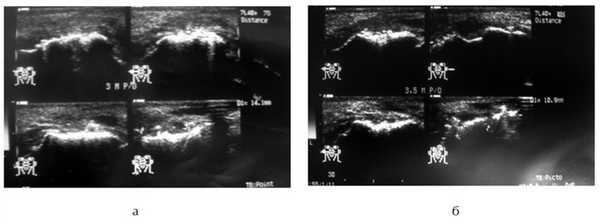

По данным УЗИ, стадия остеопороза регенерата длится от 3 до 6 мес, что эхографически проявлялось увеличением толщины эхогенного слоя. Через 6 мес происходило созревание регенерата, что визуализировалось в виде непрерывной полосы высокой эхогенности (стадия реминерализации). Через 1 год отмечали снижение высоты костного регенерата у 12 (16%) человек (рис. 4).

Рис. 4. УЗИ костного регенерата: а — через 6 мес после костной пластики; б — через 1 год после костной пластики.